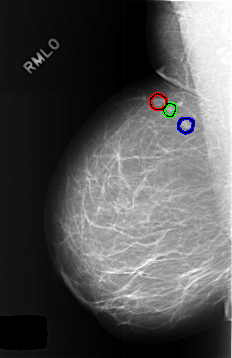

C_0446_1.RIGHT_MLO

RIGHT_MLO LINES 5728 PIXELS_PER_LINE 3712 BITS_PER_PIXEL 12 RESOLUTION 50 OVERLAY

FILE: C_0446_1.RIGHT_MLO.OVERLAY

TOTAL_ABNORMALITIES 3

ABNORMALITY 1

LESION_TYPE MASS SHAPE LOBULATED MARGINS CIRCUMSCRIBED

ASSESSMENT 3

SUBTLETY 5

PATHOLOGY BENIGN_WITHOUT_CALLBACK

ABNORMALITY 2

LESION_TYPE MASS SHAPE ROUND MARGINS CIRCUMSCRIBED

ABNORMALITY 3

LESION_TYPE MASS SHAPE OVAL MARGINS CIRCUMSCRIBED